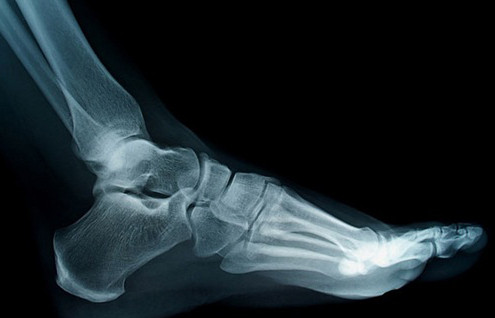

Xương không phân bố đều trên khắp cơ thể. Chúng tập trung chủ yếu ở bàn tay và bàn chân. Mỗi bàn tay có 27 cái xương và mỗi bàn chân có 26 cái. Tổng cộng hai bàn tay và hai bàn chân có 106 xương, chiếm hơn một nửa số xương trong cơ người. Ảnh: Shutterstock